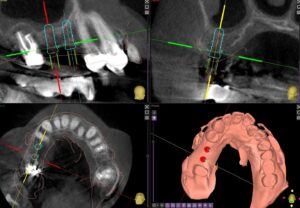

70代男性右の上下にロングスパンのブリッジが入っています。しばらくはそのまま定期検診を行っていましたが、右上7の根尖病巣に痛みを生じ、同じようにブリッジをすると負担がかかりますので、右上65にインプラント埋入を計画しました。

コンピュータガイドでしっかり位置決めを行います。やや上顎洞にかかるのでソケットリフトという手術を併用しました